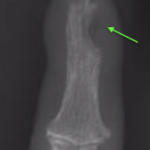

Carpal tunnel syndrome affects the median nerve that travels through a space that connects the forearm and hand at the front of the wrist. Pressure on the nerve, from many possible causes, can lead to a slowing of the electrical signals that supply sensation to the thumb, index and middle finger. It can lead to tingling and numbness in these fingers or the whole hand and can often be worse at night time.